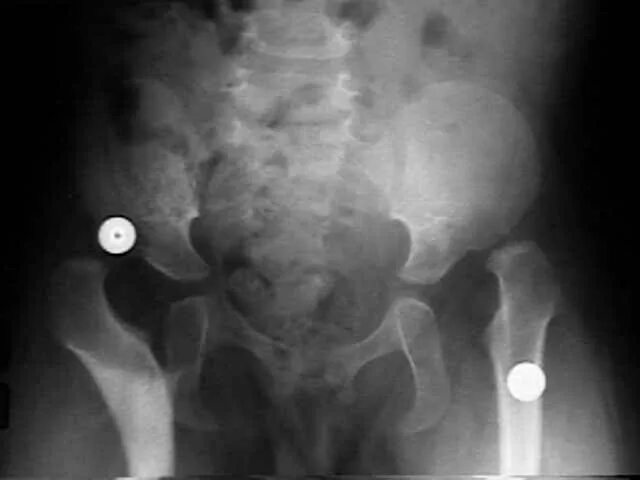

Вывих тазобедренного у взрослых